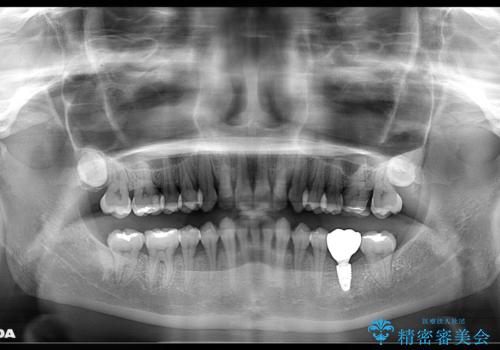

様々な治療プランを患者さんと相談させて頂き、最終的にインプラントで噛み合わせを回復させていくこととなり、まず悪くなっている歯を抜歯することから開始しました。